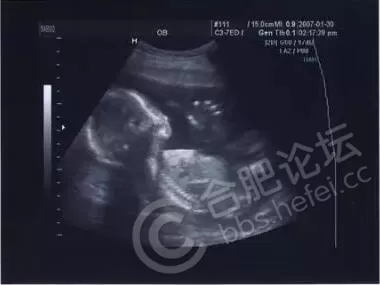

2. 男性胎儿会在母亲子宫里勃起

医学研究发现,男女婴儿在子宫内都可能产生手淫的举措。超声波图像曾抓拍到男婴的勃起图片,不过由于生殖器官差异的原因,只有男性能在X光片上看出来。